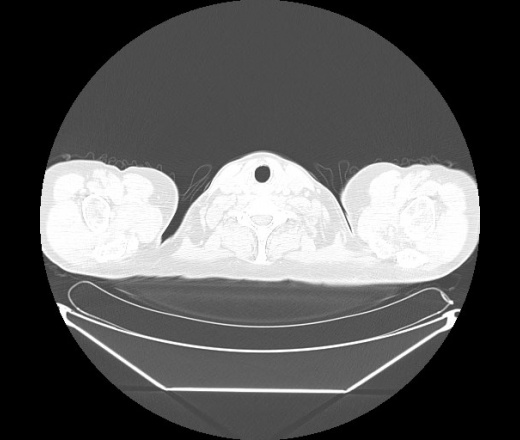

М. 1984 г.р.  Лихорадка 39, кашель , одышка.. и надоевший всем вопрос- "типично ли для ковид?" ( в настоящее время на него обязательно нужно дать ответ в своем протоколе)

На мой взгляд нетипично для ковид: много центрально-расположенных поражений, лобарное поражение нижней доли слева. 50/50

Не типичая картина для ковид.

КТ-признаки двусторонней бактериальной пневмонии.

Все верно, здесь абсолютно нетипичная картина, несмотря на матовое стекло с ретикулярными изменениями, но почему-то  посчитали иначе. Кстати,  "малыша" не заметили)?

Добавил 6 день

Что за малыш? Будущий абсцесс? Не заметил. Только о туберкулёзе подумал

+ 1?  Зона очень похожа была на формирующийся абсцесс, даже по рентгенпризнакам. Еще хотела спросить, но постеснялась. А на контроле видно

да, это я о абсцессе.